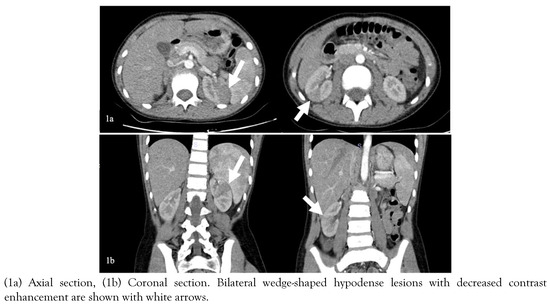

Due to the acute abdomen clinical finding in Case-2 and the significant CVA tenderness in both cases (bilateral in Case-1 and unilateral in Case-2), contrast-enhanced abdominal computed tomography (CT) was performed for differential diagnosis. In Case-1, nonhomogeneous hypodense mass-like lesions with decreased contrast enhancement in both kidneys were detected (Figure 1). In Case-2, a similar lesion was seen in the lower pole of the right kidney (Figure 2). Both cases were diagnosed with AFBN since these lesions were specific for it.

Figure 1.

Images of contrast-enhanced abdominal CT of Case-1.

Costovertebral angle tenderness is one of the specific indicators for kidney pathology and is often seen in acute pyelonephritis [12]. However, it may present in other diseases such as nephrolithiasis, kidney abscess, vesicoureteral reflux, obstructive pathologies of the urinary tract, retrocecal appendicitis, retroperitoneal abscess [13]. In a patient presenting with fever and CVA tenderness, the clinician should consider first upper UTI, among other diagnoses. In selected cases, imaging techniques can be used for differential diagnosis. Herein, due to the presence of CVA tenderness, we performed contrast-enhanced CT imaging, which showed hypodense wedge-shaped kidney lesions indicating AFBN (Figure 1 and 2) [14].

Early diagnosis and effective treatment are essential in terms of preventing renal scars and morbidity such as hypertension, proteinuria, and renal failure [18]. The diagnosis of AFBN is based on radiologic examinations. In many cases, there is no finding on kidney ultrasonography (USG), although it may show nephromegaly, focal lesions with poorly defined irregular margins. Contrast-enhanced abdomen CT is the gold standard imaging technique for the diagnosis of AFBN. Herein, both cases had no finding on kidney USG. The lesions were observed on CT as the typical wedge-shaped, poorly defined hypodense lesions after contrast-medium administration [14]. The DMSA scan of the kidneys may help in the diagnosis of AFBN and the detection of renal scarring during follow-up [19]. In Case-1, the diagnosis of AFBN was supported with the DMSA scan. In Case-2, the DMSA scan in follow-up shows no scars indicating the effective treatment.